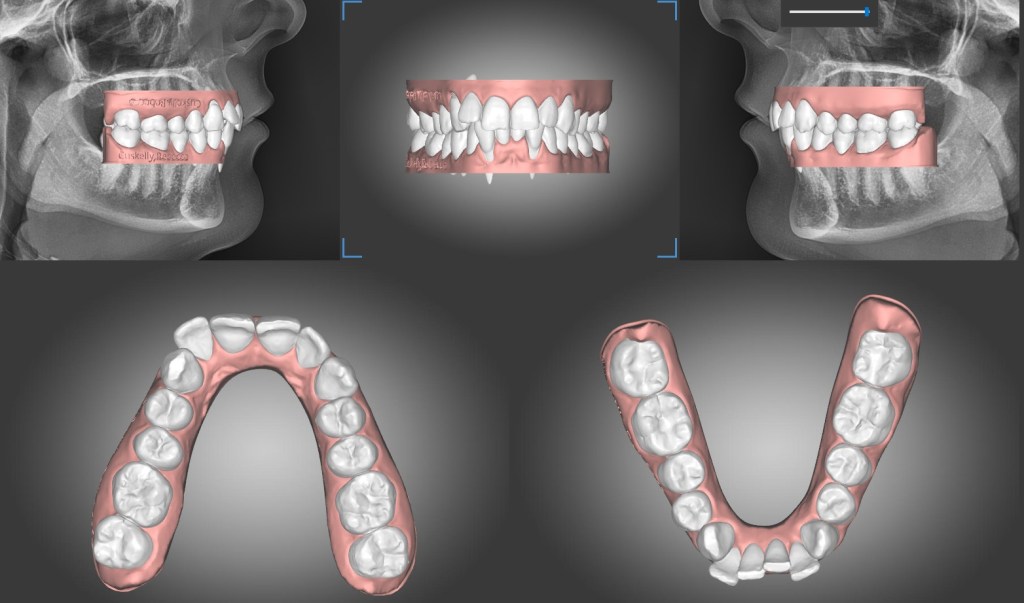

Case selection

Functionality is the reason that I, as a dentist, prescribe orthodontic treatmen; to give my patient a better occlusion/ bite and to align gtheir teeth for easier maintenance. Cosmetic is the patient’s call. However it should be noted that functionality and cosmetic are not mutually exclusive. Generally functional occlusion that is aligned is cosmetically pleasing. The converse may not be true.

To be able to deliver in house aligners a clinician should have

- digital scanner

- orthodontic software to plan movement

With experience and careful planning the clinician becomes more confident of delivering great clinical outcomes consistently. Having just the first two components, the digital scanner and the software, would already give the clinician the advantage of control over the case compared to using a third party provider.